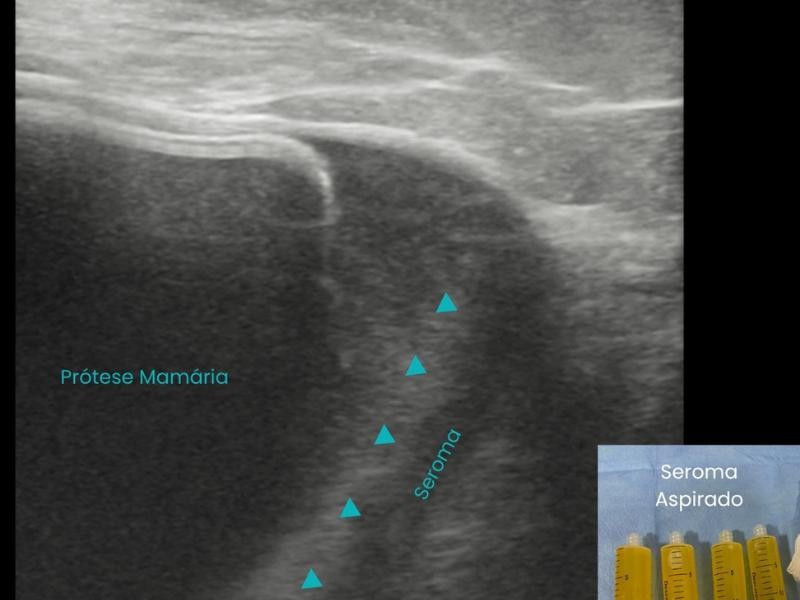

A Esclerose de Cisto consiste na drenagem do líquido contido na lesão, seguida da introdução de um agente esclerosante para evitar a recidiva do cisto. O procedimento é realizado com precisão através de imagem em tempo real, como ultrassonografia ou tomografia, garantindo segurança e eficiência.

Primeiramente o paciente recebe pomada anestésica e anestesia local para evitar qualquer incomodo. O procedimento é realizado com auxílio de ultrassom ou tomografia para guiar a introdução de uma agulha dentro do cisto. O líquido é aspirado, e em seguida, um agente esclerosante, como álcool absoluto e polidocanol, é injetado para obliterar a cavidade e impedir sua recidiva.